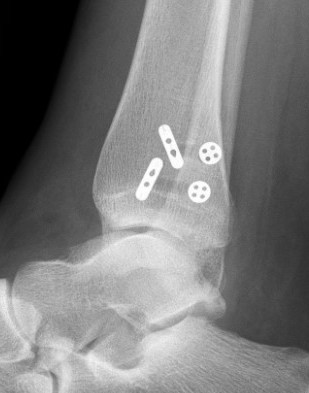

Weber A fibular fracture

Definition

Fracture below level of syndesmosis

Fibular avulsion fracture

Management

Stable

Full weight bear